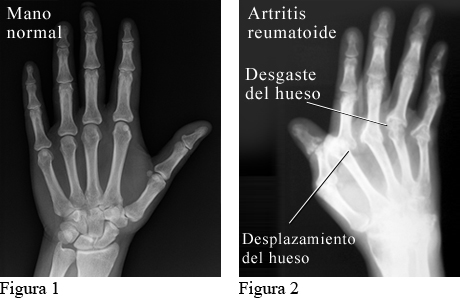

Radiografía que muestra artritis reumatoide en las manos

La figura 1 es cortesía de Intermountain Medical Imaging, Boise, Idaho. La figura 2 es cortesía de Paul Traughber, M.D., Boise, Idaho.

La radiografía de la izquierda muestra una mano normal.

La radiografía de la derecha muestra una mano con artritis reumatoide avanzada. La "erosión del hueso" significa que el cartílago y el hueso se han desgastado. El "desplazamiento del hueso" significa que un hueso se ha salido de su posición normal. Esta radiografía muestra cómo la erosión ósea y el desplazamiento óseo pueden cambiar la forma de la mano.